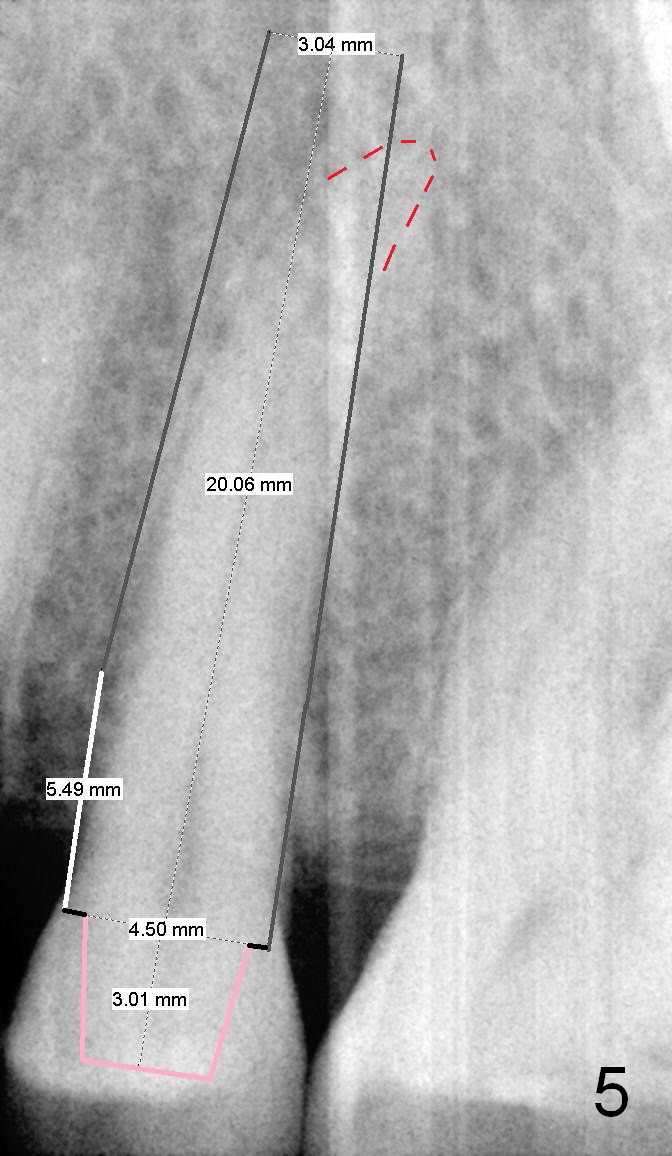

A 67-year-old lady (CC) has an implant at the site of #3, which replaces the fractured tooth (Fig.1). Recently the tooth #13 also fractures subgingivally (Fig.2). The tooth has a long and curved root. All of these suggest that the patient is a bruxer. The bone density is high. After extraction and placement of Clindamycin gauze in the socket, a 2 mm pilot drill is used to start osteotomy ~17 mm from the gingival margin, followed by 2.5 mm reamer ~ 17 mm, and 3 for 14 mm. If the socket looks small (mesiodistally), the goal is to place 4.1x14 (Fig.3) or 13 mm (Fig.4) implant. Otherwise use 4.5x17 mm Tatum tapered tap at 14 mm and plan to place a 4.5x13 or 14 mm implant. If it is difficult to insert an implant, use one size smaller drill from its original cassette or use 5x17 mm tap at 11 mm (to open up the entrance of the osteotomy). If the implant or tap is being deviated buccally while it is placed, use a Lindermann bur from Bicon Restorative plastic box to remove the bone from the palatal wall. When the side-cutting drill is cleaned, keep it in the Bicon Surgical Cassette. If the bone density turns out to be low, osteotomy depth will be 20 mm instead (Fig.5). When the flutes of 2.5 and 3 mm reamers collects bone particles, the bone density is high.